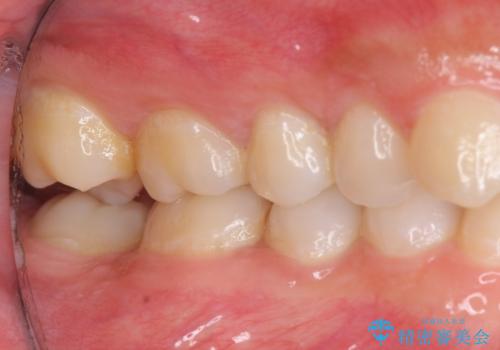

右上下の奥歯もすれ違い咬合も、治療で改善しています。